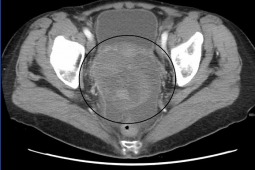

Cediranib w leczeniu kobiet chorych na nawrotowego raka jajnika.

Podczas ECC (European Cancer Congres) 2013 zostały zaprezentowane wyniki badania 3 fazy ICON6 – określającego skuteczność cediranibu zastosowanego razem z chemioterapią zawierającą pochodną platyny w leczeniu chorych, u których wystąpił nawrót raka jajnika po okresie dłuższym niż 12 miesięcy od zakończenia wcześniejszego leczenia schematem zwierającym pochodną platyny.